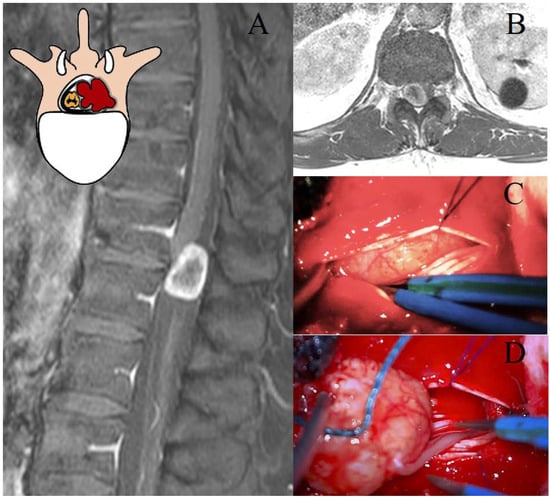

The Eden class II lesions are rarer and less studied in the literature [3]. There is a lack of evidence regarding their optimal management [3,8]. Due to the rarity of the pathology, these tumors are often investigated together with the cervical and lumbar ones, preventing the drafting of reliable recommendations [25]. The presence of sacrificable thoracic nerve roots and the complex anatomy of the posterior mediastinum justify considering these lesions as a distinct entity [7]. In our opinion, the perception of spinal instability in these lesions warrants further investigation [26]. In our study, bilateral LCT and TPD were the investigated approaches. TPD presumably required significantly longer surgical times to create larger surgical corridors [19,29], yet did not result in substantially higher GTR rates compared to LCT (100% vs. 88%). This aspect remains an open question. Further well-structured and focused studies are needed to determine the most appropriate surgical approach for these rare Eden class II lesions. Furthermore, the resection of the ipsilateral pedicle and articular facet would presumably raise concerns regarding thoracic spinal instability (Figure 2) [19,29]. Therefore, while our study describes the enrolled cases, it does not allow us to definitively advocate the best surgical approach for these lesions. The need for secondary stabilization has been explored in studies on thoracic disk herniations [19,27]; however, these findings may not be directly applicable to intradural tumors [16].

Figure 2. Representation of a T5–T6 schwannoma, Eden Type II. (A) Preoperative sagittal T1-weighted MRI with contrast, showing a lesion at the right T5–T6 level with both intradural-extramedullary and foraminal extension. (B) Axial MRI demonstrating the extradural and foraminal components of the lesion, with wide erosion and remodeling of the bone vertebral structure. (C) Intraoperative view following a laminectomy, exposing the tumor. (D) The transpedicular exposition of a tumor, with the demolition of the ipsilateral pedicle and articular facet.